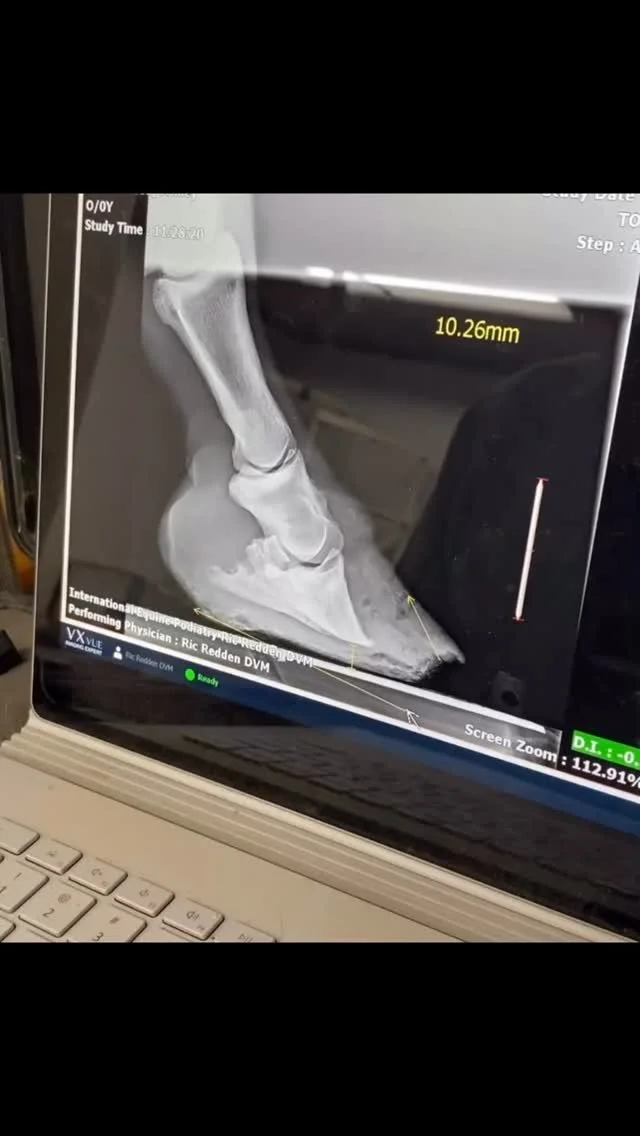

Está capacitado para interpretar radiografías y venogramas del casco, evaluando estructuras óseas, cápsula solar, espacio vascular y tejidos internos.

Internado uno a uno durante tres meses en el International Equine Podiatry Center (IEPC) junto al Dr. Ric Redden, considerado el padre a nivel mundial de la podología equina y fundador de NANRIC, marca de referencia en herraduras terapéuticas. Formación avanzada en herraje mecánico, interpretación de radiografías y venogramas y en el tratamiento de casos complejos como laminitis, síndrome navicular, talones colapsados, caballos topinos y numerosas patologías.

Internado en Rood & Riddle Equine Hospital en Lexington (Kentucky) junto a Scott Morrison, un destacado podólogo equino y herrador especialista en biomecánica, herrado terapéutico y tratamiento de afecciones complejas del casco. Una referencia internacional en el campo de la podología equina y la rehabilitación locomotora.

x2 Dr. Ric Redden’s Equine Podiatry Course

x2 Curso intensivo de Podología Equina impartido por el Dr. Ric Redden, referente mundial en el tratamiento de patologías del casco. Un enfoque práctico y avanzado para comprender la biomecánica, diagnosticar correctamente y aplicar técnicas efectivas en casos complejos como laminitis, deformidades o cojeras crónicas.

Internado uno a uno de tres meses junto al Dr. Ric Redden, considerado el padre de la podología equina a nivel mundial y fundador de NANRIC, marca de referencia en herraduras terapéuticas. Formación avanzada herraje mecánico, en interpretación de radiografías y venogramas y en el tratamiento de casos complejos como laminitis y otras patologías.